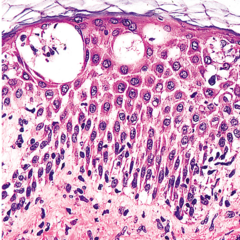

dermis

Front

what layer of this skin is this

Back